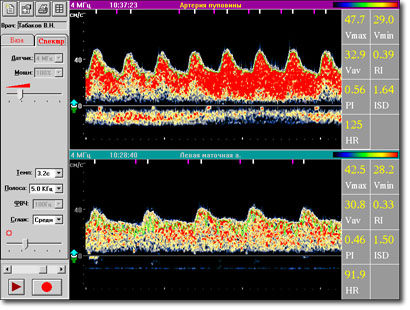

Основные характеристики Встроенная акушерская программа с нормативными значениями RI для маточных артерий и артерий пуповины с учетом срока беременности Автоматический расчет акушерских индексов во время обследования Быстрая подготовка отчета на основе специализированных акушерских шаблонов Многооконная планировка экрана (до 8 спектров на экране) Встроенная база данных Просмотр спектров из базы данных со звуковым сопровождением

Ультразвуковой допплеровский прибор для диагностики периферического и мозгового кровообращения на основе спектрального анализа скорости кровотока. Область применения неврология сосудистая хирургия нейрохирургия общеклиническая диагностика педиатрия офтальмология Возможности Многоцелевые ультразвуковые исследования кровотока интра-, экстракраниальных и периферических сосудов с помощью унифицированного набора датчиков: 2 МГц, 4 МГц, 8 МГц Высокая чувствительность прибора, обеспечивающая быстрый поиск и устойчивую локацию сосудов Высокое качество цветного / полутонового изображения спектра кровотока Специальные режимы обработки спектра в реальном времени: сжатие, сглаживание Разнообразная постобработка спектральных данных Специализированная база данных результатов обследований Расчет в автоматическом и ручном режиме основных медицинских индексов: RI, PI, ISD, STI; основных параметров кровотока: HR, VS, VD, VA Организация просмотра спектра в режиме кинопетли (до 16 экранов) Поддержка средств передачи информации по сетям и телефонным линиям Технические характеристики